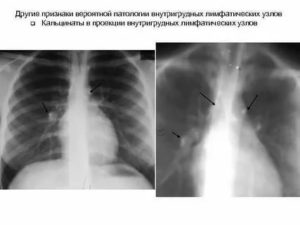

Кальцинаты во внешних лимфатических узлах определяются как плотные образования. Во внутренних — патологические изменения можно увидеть при рентгенографии, магнитно-резонансной или компьютерной томографии.

При туберкулезе внутригрудных лимфатических узлов (бронхоаденит), которая встречается преимущественно в детском и подростковом возрасте (у «виражных» и непривитых детей), часто специалисты обнаруживает на рентгене кальцинаты в виде равномерно расположенных округлых теней.

Кальцинаты в легких при туберкулезе внутригрудных лимфоузлов — это замещение известью участков воспаления и некроза, которые появляются в результате острого инфекционного процесса.

Определить разновидность туберкулеза может врач на основании данных рентгенодиагностики.